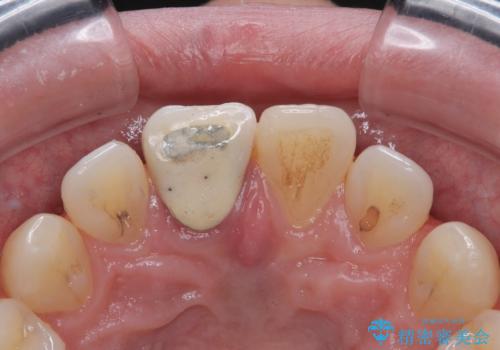

- 数年前に前歯のセラミック治療を行い、そのやり替えを希望して来院された患者様です。

先端が欠けてしまっていて、色も少し不自然な印象があります。

空隙がある歯並び改善のため、矯正治療も提案しましたが希望せれず、隣の歯も一緒に被せものにして、

大きさをそろえることも希望されなかったため、一本だけやり替えていくととしました。